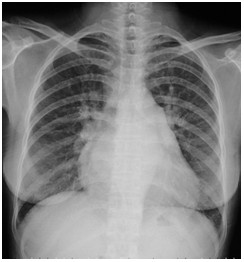

临床助理医师实践技能考试模拟试题:“ X线-正常胸片 ”影像诊断!

2022-03-29

2022年临床助理医师实践技能考试影像诊断模拟题(2分)

临床助理执业医师实践技能考试第一站例题:影像诊断